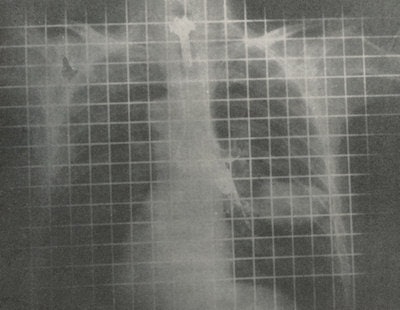

An early bronchogram using the stationary crisscross Bucky grid with grid lines visible.Bucky came up with a possible solution, which was to move his grid so the shadows of the strips were no longer visible. It is interesting that quite independently in 1917 Eugene Caldwell (1870-1918) from New York had the same idea of moving the grid to remove the shadows. A third investigator, Hollis Potter (1880-1964) from Chicago, was unaware of the previous publications and presented his ideas at meetings of the American Roentgen Ray Society (ARRS) in 1915. Potter described a diaphragm that he adapted for fluoroscopy and consisted of a rotating circular disc with radiating strips to absorb the scatter.

Interception of scattered rays by a grid.These early grids with the crisscross pattern were neither successful nor popular. However, Potter was aware that a moving wire did not cast a shadow on an x-ray plate, and so he realized this would also happen if a lead strip that moved uniformly across the beam was used. Potter created a series of parallel strips, and although this should only have absorbed a portion of the scattered radiation, Potter found not only was the total amount absorbed similar to that of the crisscross Bucky grid, but also it was much easier to manufacture.